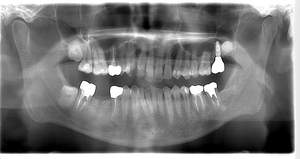

インプラント治療の症例1

レントゲン写真

- 透過像

| 年齢 | 50代・男性 |

|---|---|

| 主訴 | 右下歯が疼く |

| 治療内容 | ・右下6番インプラント ※1:FGG(遊離歯肉移植術)とは、足りない歯ぐきを上顎から上皮を切り取り移植する外科手術 |

| 治療費 | 合計:902,000円(税込) ■内訳 |

| 治療期間 | 9ヵ月 |

| 治療方針 | 右下の当該歯は歯根破折により保存不可能と診断しました。歯周疾患も伴っていたため抜歯後に骨吸収※1が大きく起こることが予測できました。チタンメッシュ併用骨再生誘導法(GBR※2)を選択しインプラント埋入と同時に行い自然な歯槽骨のラインを再現しました。またGBRを行う際にインプラント辺縁の付着歯肉の減少が起こる為、遊離歯肉移植術(FGG※3)を行い清掃性を考慮した形態に仕上げました。 ■治療方針の解説 治療した右下の歯をレントゲンで撮影したところ根本の部分に黒く写る箇所があり「根尖性慢性周囲炎※1」と診断。また歯周病も進行していました。 ※1 骨吸収・・・歯槽骨という歯を支える骨がなくなっていくこと |

| 担当者所見 | 主訴の右下だけでなく歯茎の腫れ、発赤があり不良補綴や不良充填など他にも治療箇所が多数ありました。プラークコントロールが不良であった為まずはブラッシング指導を行いセルフケアの重要性を理解していただくところからスタートしました。 右下6番の歯はインプラント治療を行なった結果審美的にも機能的にも患者様の満足を得ることができました。骨造成と歯肉移植も行なった為インプラントを支える十分な歯周組織の獲得ができたと思っております。 |